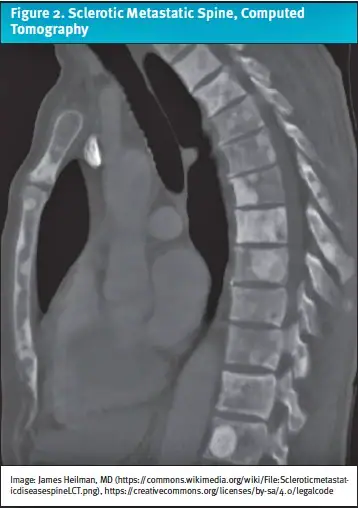

- Persistent back, hip, or rib pain in a patient with prostate cancer should raise a high suspicion for fracture. Order x-rays and arrange for urgent ED evaluation for a CT/MRI (Figure 2).

The differential diagnosis in this patient included primary malignancy, metastatic disease, fracture, osteomyelitis, or epidural compression syndrome such as cauda equina syndrome. In the ED, computed tomography (CT) and magnetic resonance imaging (MRI) of the spine revealed sclerotic lesions in the thoracic spine, suggestive of osteoblastic bone metastases. He was ultimately diagnosed with prostate cancer with bone metastases.

Diagnosis: The patient was referred to the emergency department for further evaluation. Subsequent computed tomography and magnetic resonance imaging of the spine revealed sclerotic lesions in the thoracic spine, suggestive of osteoblastic bone metastases. He was ultimately diagnosed with prostate cancer with bone metastases.